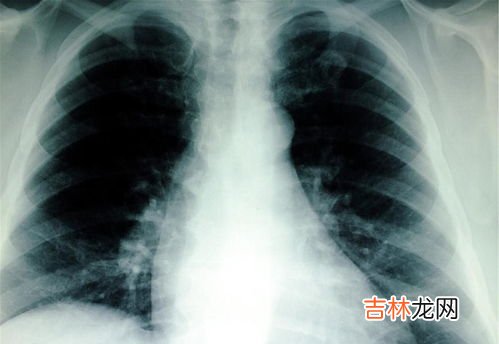

如果处于新型冠状病毒流行期,曾经密切接触过新冠肺炎感染患者的人群,只要出现了新型冠状病毒感染的相关症状,就要及时前往医院就医 , 进行核酸和抗体的检查,确定是否存在新型冠状病毒感染的情况 , 为了排除是否患有新型冠状病毒肺炎 , 可能还需要进行胸部CT检查 。

判断新型冠状病毒感染,需要经过核酸检测和抗体检测 , 才能明确诊断 。部分患者可能还需要进行胸部CT检查后,才能完全排除新冠肺炎的可能 。